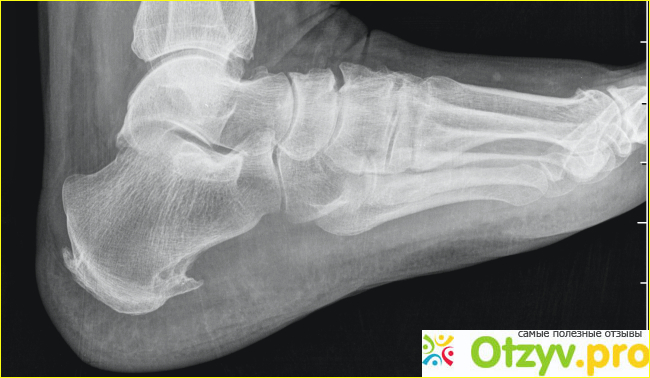

Пяточная шпора представляет собой костное разрастание, возникающее вследствие нарушения обмена кальция. Разрастание имеет клиновидную форму, появляется на пяточной кости, на её подошвенной поверхности.

Костное разрастание (остеофит) причиняет мучительную боль, шип может достигать длины 1,2 см, сдавливая окружающие ткани. Это новообразование внешне абсолютно незаметно, но его можно определить обычным надавливанием на пятку.

Обычно о развивающемся новообразовании сигнализирует сильная боль. Но в некоторых случаях образование формируется без всяких симптомов. Нередко пяточную шпору обнаруживают случайно, во время рентгенологического обследования, вызванного другими показаниями.

Чтобы правильно поставить диагноз, врач направит на рентгеновское исследование. При необходимости нужно будет пройти УЗИ.